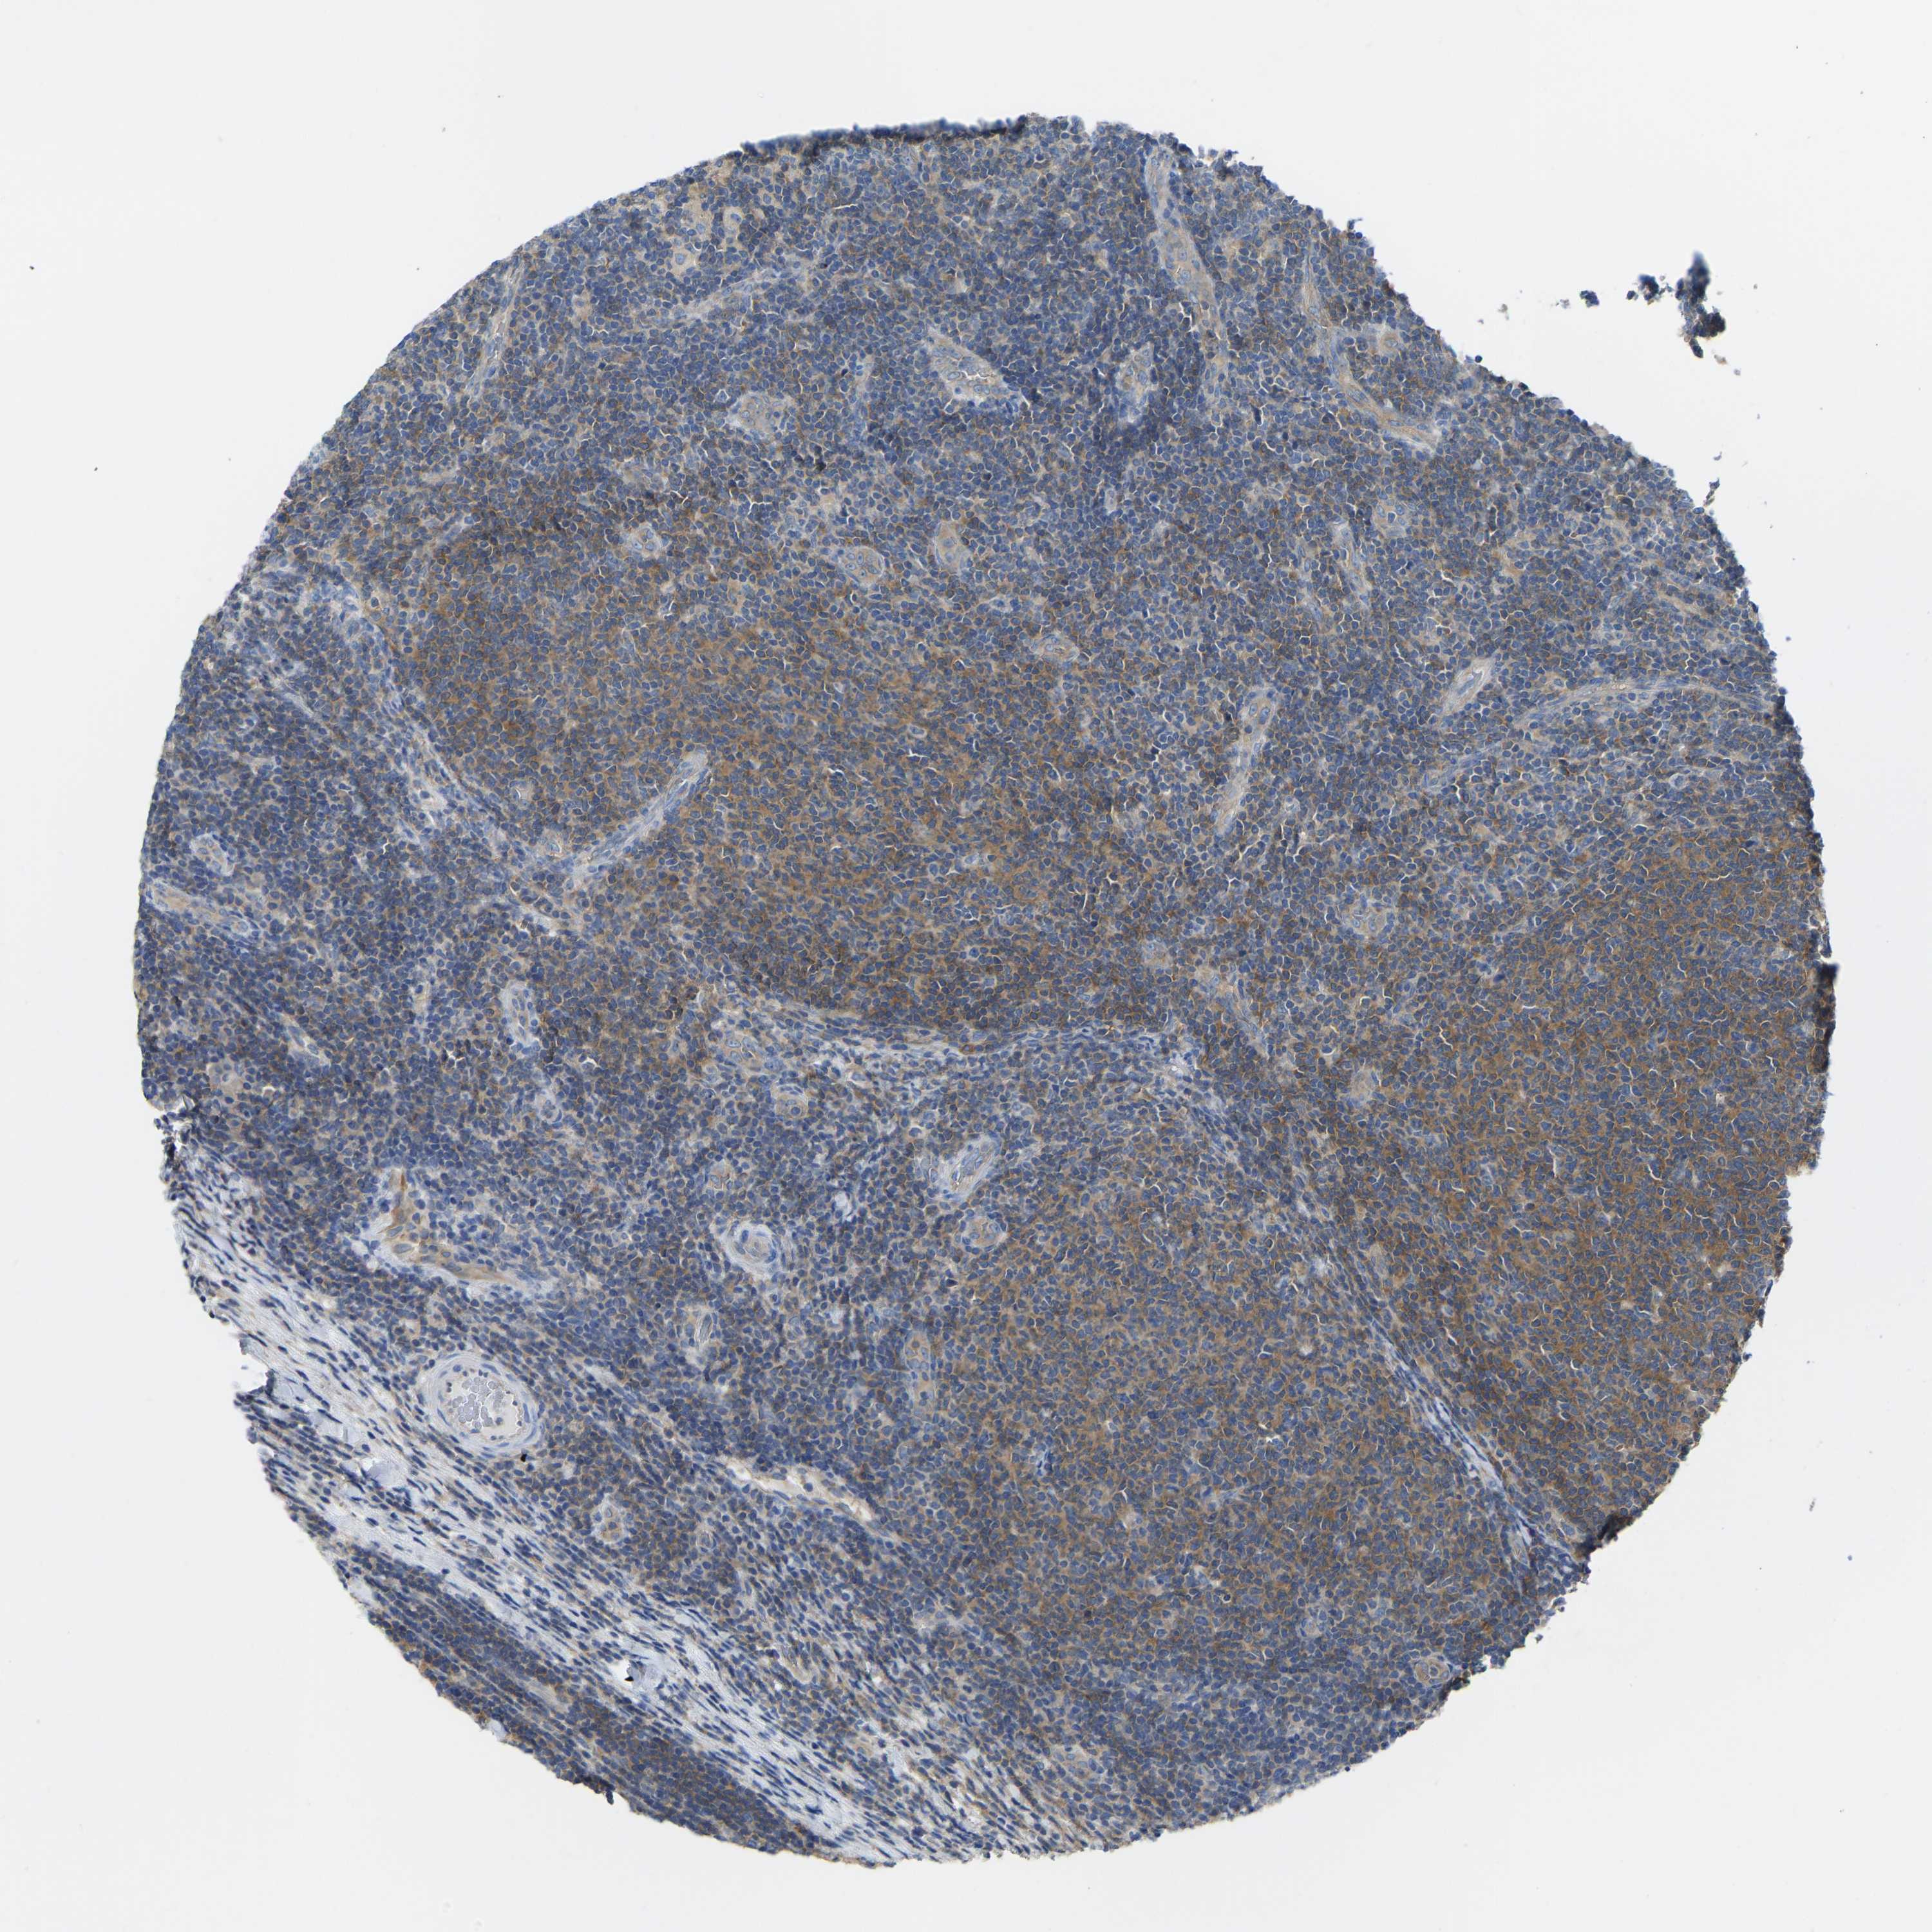

CANCER LYMPHOMA Show tissue menu

LYMPHOMA - Protein expressioni

A mouse-over function shows sample information and annotation data. Click on an image to view it in a full screen mode. Samples can be filtered based on level of antibody staining by selecting one or several of the following categories: high, medium, low and not detected. The assay and annotation is described here.

Antibody stainingi

Antibody staining in the annotated cell types in the current human tissue is reported as not detected, low, medium, or high, based on conventional immunohistochemistry profiling in selected tissues. This score is based on the combination of the staining intensity and fraction of stained cells.

Each image is clickable and will lead to virtual microscopy that enables deeper exploration of all samples and also displays staining intensity scores, fraction scores and subcellular localization as well as patient and tissue information for each sample.

Antibody HPA012778

Antibody CAB018581

Staining

High

Medium

Low

Not detected

Intensity

Strong

Moderate

Weak

Negative

Quantity

>75%

75%-25%

<25%

None

Location

Nuclear

Cytoplasmic/membranous

Cytoplasmic/membranous,nuclear

Hodgkin's disease, NOS

Malignant lymphoma, non-Hodgkin's type, High grade

Malignant lymphoma, non-Hodgkin's type, Low grade